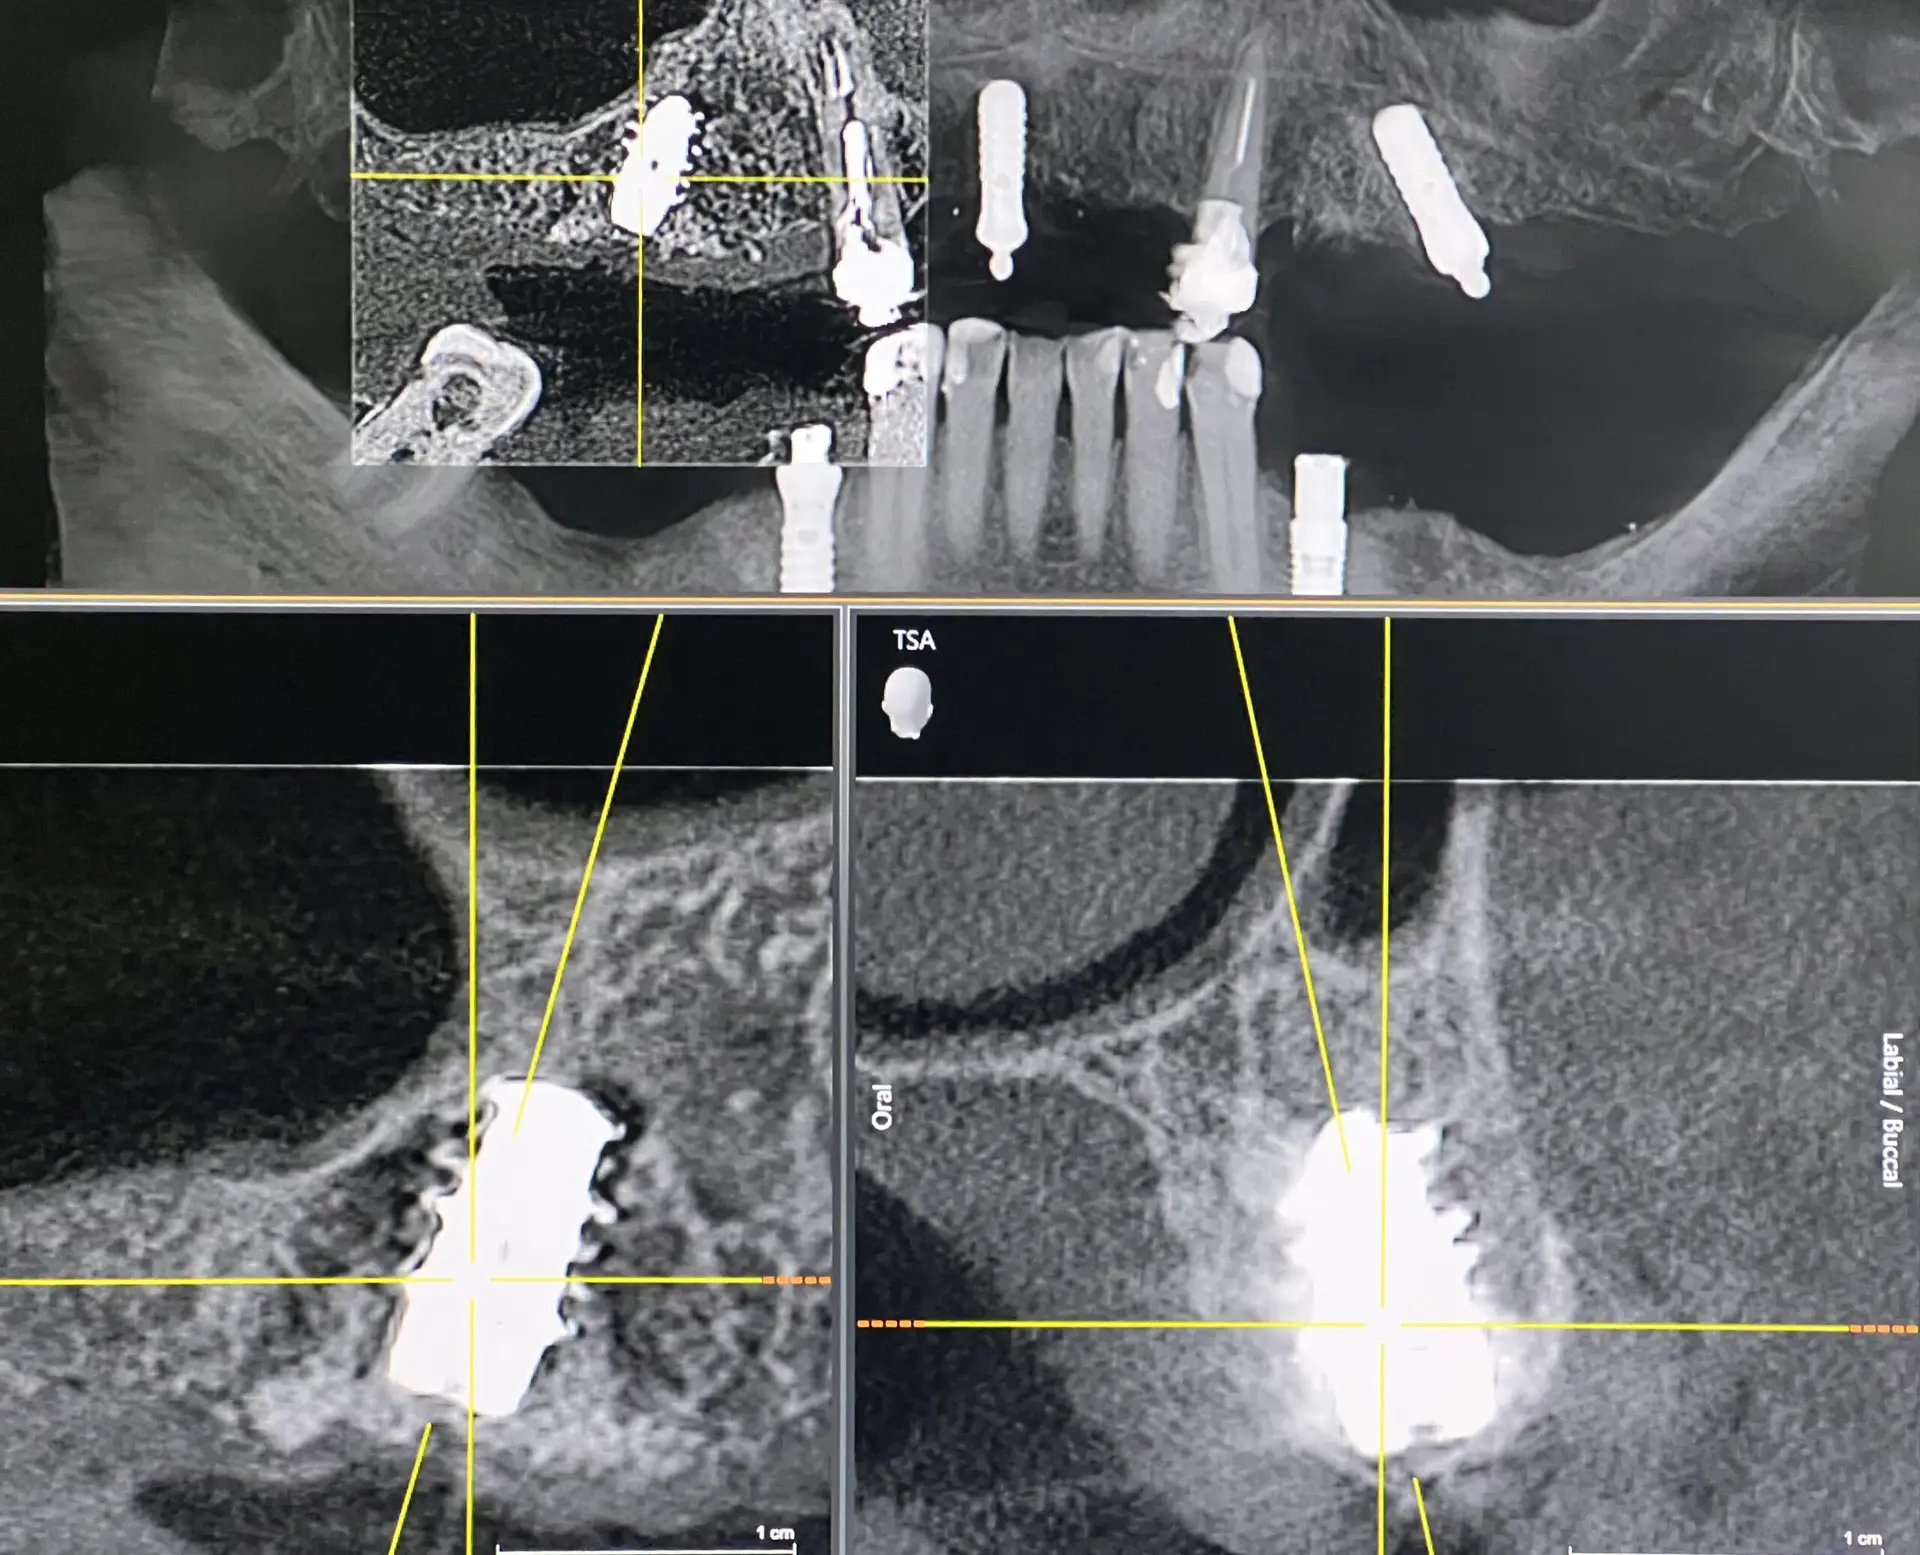

Digitale Röntgendiagnostik

Digitale Röntgenaufnahmen ermöglichen eine genaue Darstellung von Zähnen, Wurzeln und Kieferknochen. Dadurch können versteckte Probleme erkannt und Behandlungen präzise geplant werden.

Digitale Röntgenbilder

Digitale Röntgenaufnahmen ermöglichen eine genaue Darstellung von Zähnen, Zahnwurzeln und Kieferknochen, sodass auch versteckte Probleme frühzeitig erkannt werden können.